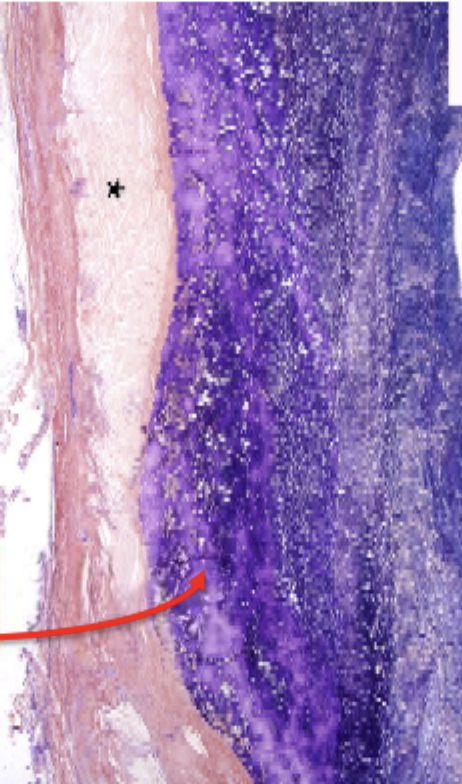

what is the blue in this image

fibrin

lines of zahn

alternating layers of platelets and blood cells

only form when the blood is moving quickly - arterial not venous thrombi

canaliculi

perpendicular to lines of zahn

allow more porous parts to drain through the thrombus

important for fibrolytic zone - allows fibrolytic zone to drain down

fibrinolytic zone

fibrin turns from a darker blue to a lighter colour